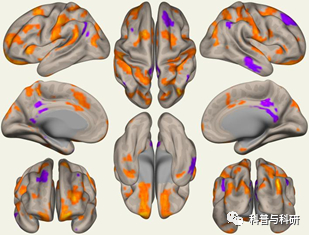

VBM、SBM讲解、操作 |

1、脑结构分析及VBM、SBM分析原理介绍 2、VBM、SBM分析流程、操作步骤详解(CAT12) 3、基于CAT12的皮层数据预处理详解 4、皮层统计分析 5、结果可视化软件实操 |

FreeSurFer脑皮层厚度预处理及统计分析 |

1、Linux简单命令学习 2、FreeSurFer皮层厚度处理及文件说明(thickness,sulc,curv) 3、基于组水平的皮层厚度统计 |

1、海马亚区分割 2、特定脑模板皮层厚度提值 3、结果汇总与可视化操作 |

(2)基于表面(surface)的脑影像数据

基于Freesurfer对数据进行预处理、创建FSGD和mtx、Glm分析、结果报告。